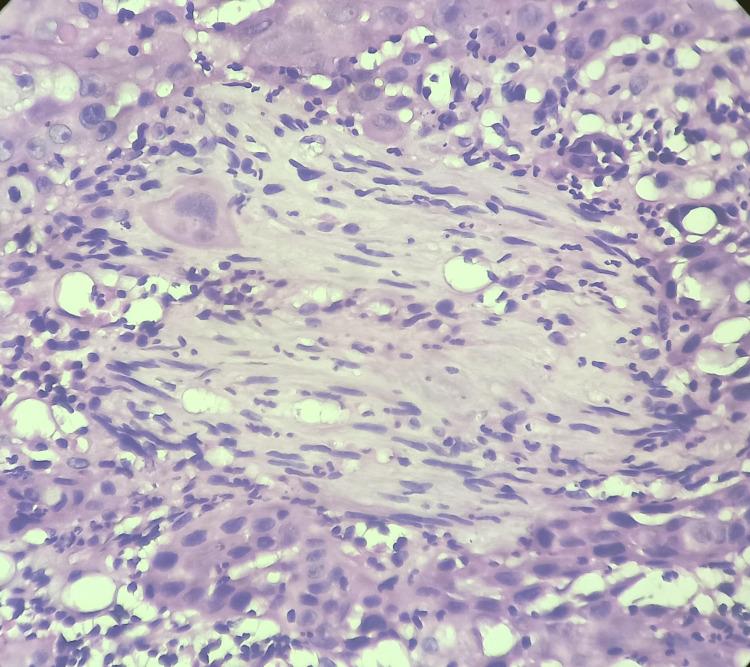

Oral squamous cell carcinoma is associated with severe morbidity, recurrence of tumor, and reduced survival rate despite advances in treatment. Perineural invasion (PNI) is associated with neurotropic malignancy. PNI is due to the tropism of cancer cells toward nerve bundles in tissue. The aim of this literature review is to study the definition, patterns of PNI, Prognostic and therapeutic significance, and mechanism of PNI along with a molecular insight into oral cavity squamous cell carcinoma. Liebig type A pattern defines PNI as the presence of tumor cells within the peripheral nerve sheath & infiltration into the epineurium, perineurium, or endoneurium. Liebig type B pattern defines PNI as a tumor encircling at least 33% of a nerve. Few studies demonstrated an association between PNI and cervical metastasis which indicate poor prognosis. A higher level of expression of nerve growth factor and tyrosine kinase is associated with PNI in OSCC which can be considered as a biomarker of PNI. PNI needs to be studied in detail as it is associated with the aggressiveness of the tumor and decreased survival.